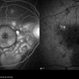

- A fluorescence angiogram of a 40-year-old-man with a Behcet's Disease on his both eyes.